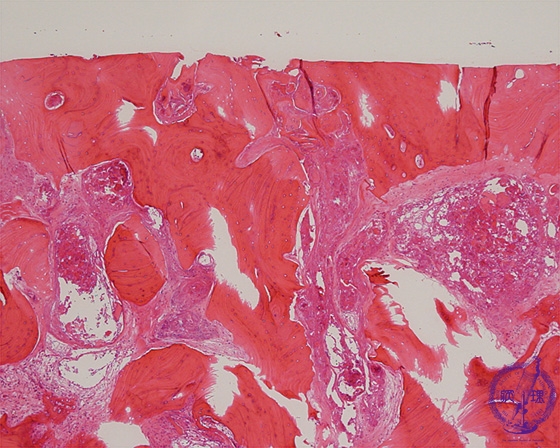

Microscopic view (HE; low power view): The area of exposed bone: Joint cartilage has completely disappeared, and underlying bony trabeculae are thickened. Compare to normal joint cartilage.

Click the image to see the enlarged image.